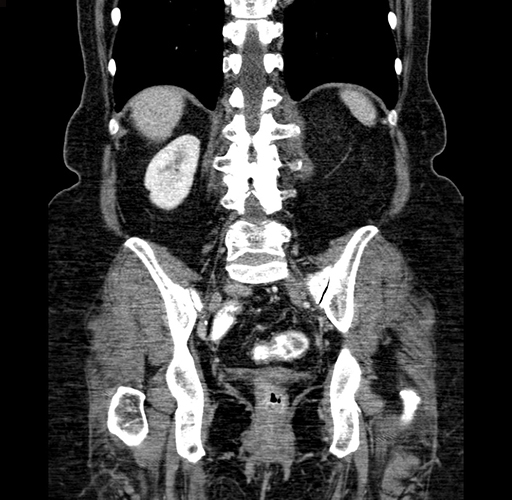

Pre-Chemo: Coronal Venous

Coronal Venous